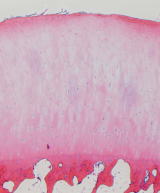

関節軟骨は表層-中間層-深層(放射層)-<tide mark>-石灰化層 の4層の層状構造をとります。石灰化層は骨(軟骨下骨)と強固に連結します。

Tide markはhematoxylin染色で濃染する線状に見える部分です。関節軟骨の厚さは1mm位から、最大の膝蓋軟骨で5mmにもなります。 関節軟骨は80%の水分、20%のマトリックスとわずかな軟骨細胞により構成されます。